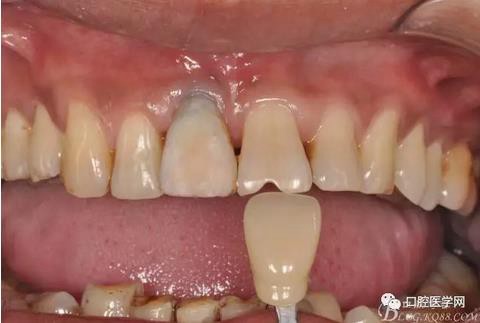

圖13 比色

圖14 烤瓷冠模型唇側(cè)照